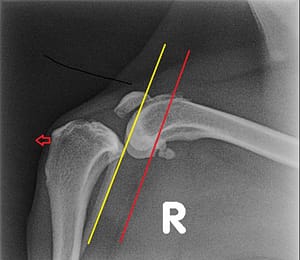

Hieronder links een foto van een gezonde knie en rechts een knie met gescheurde voorste kruisband. Hierbij valt op dat het onderbeen naar voren is geschoven bij de zieke knie.